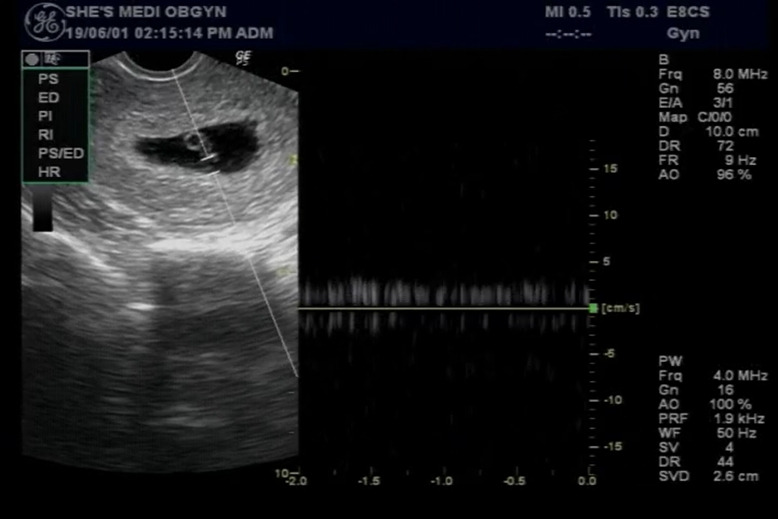

입덧이 너무 심하다 싶어 2주가 지나지 않았는데 병원을 찾았다. 의사 선생님의 예언처럼 내 입덧의 시작과 함께 아기의 심장은 힘차게 뛰고 있었다. 힘든 시간을 잘 버텨준 아기에게 감사하다는 생각이 제일 먼저 들었다. 기쁨도 잠시 언제 그랬냐는 듯 조용히 사라져 버리면 너무 슬플 것 같다는 두려움 때문이었다. 아무것도 없던 아기집에 동그란 점이 생기더니 이젠 제법 젤리곰의 형태를 갖추기 시작했다.

0.47 cm 크기의 아기는 손가락 한마디도 채 되질 않는다.

처음 신장소리 듣던 날 (6주 1일차)